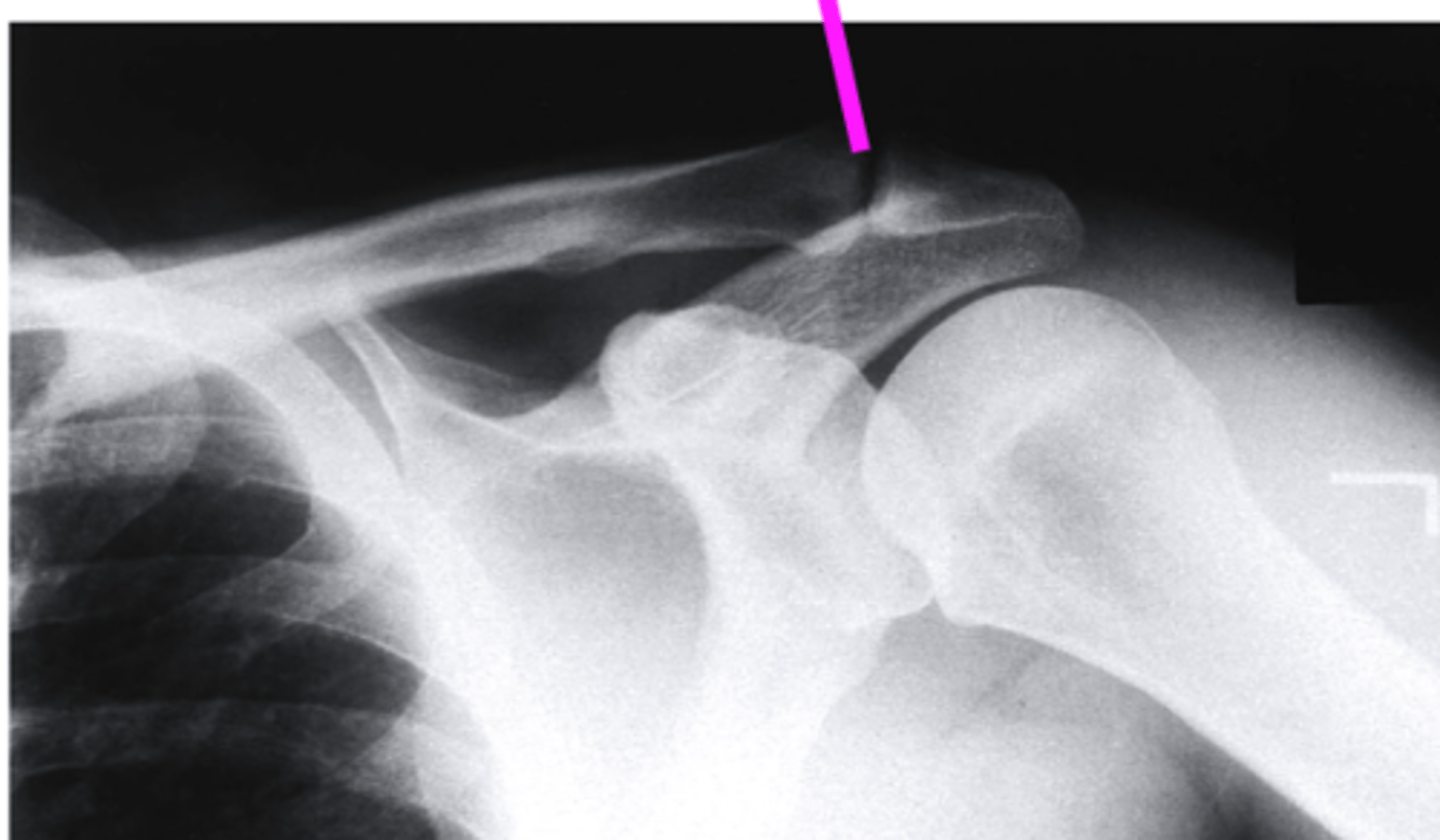

AP + ER

What view is this?

clavicle

what does the pink line point to?

spine of scapula

coracoid process

AC joint

acromion